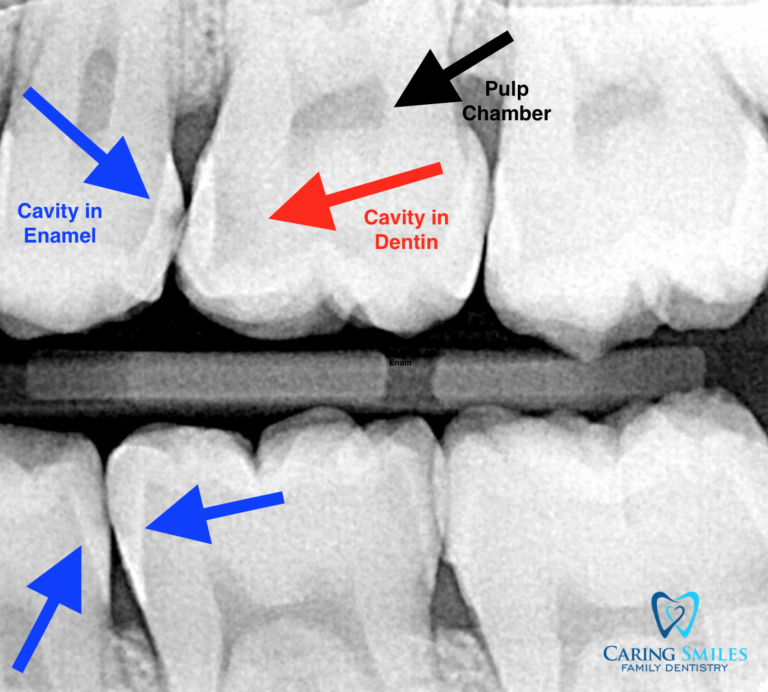

From caringsmilesfd.com

What is a Flossing Cavity and How Can I Prevent It? Caring Smiles What Are Flossing Cavities These bacteria love sugary substances — and as they feast on them, they produce acids that can harm the shiny,. Next, form a 'c' shape around each tooth and clean both sides. The good news is that flossing cavities are 100% preventable by limiting sugar intake, flossing regularly, and/or using a waterpik waterflosser. Here is a demonstration from. Flossing is. What Are Flossing Cavities.